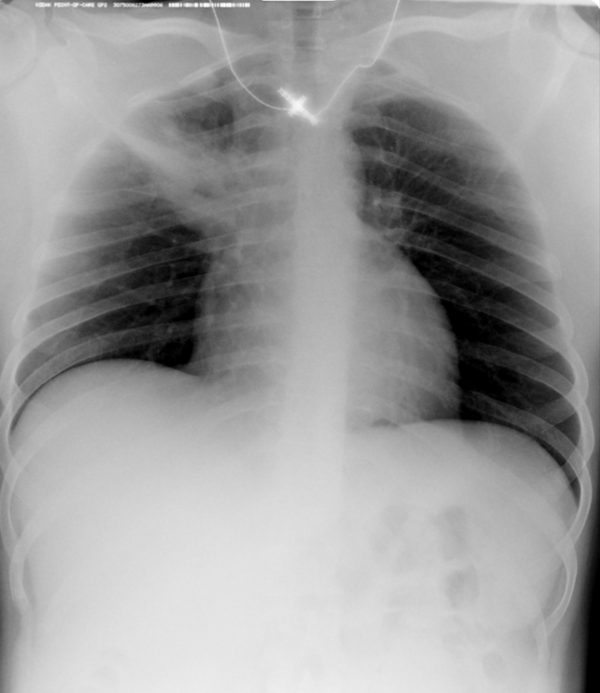

Второй наиболее частой причиной, по которой выполняется рентген грудной клетки, является травма груди с подозрением на перелом рёбер. Может показаться, что ушиб грудной клетки является несерьезным основанием, чтобы обратиться к врачу и сделать рентген. Однако приглушая боль приёмом обезболивающих препаратов, можно пропустить ряд опасных осложнений. Сломанные рёбра могут ранить легкое и вызвать пневмоторакс, т.е. скопление воздуха, или гемопневмоторакс, т.е. скопление крови и воздуха в грудной полости. Перелом трех и более рёбер может вызвать серьёзные дыхательные нарушения, что особенно опасно у пожилых пациентов. Поэтому не стоит рисковать здоровьем и необходимо сразу обратиться к врачу. Пациенты, обратившиеся в наш медицинский центр "Ваше Здоровье", смогут получить весь комплекс необходимых лечебно-диагностических мероприятий, в т.ч. рентген на дому.